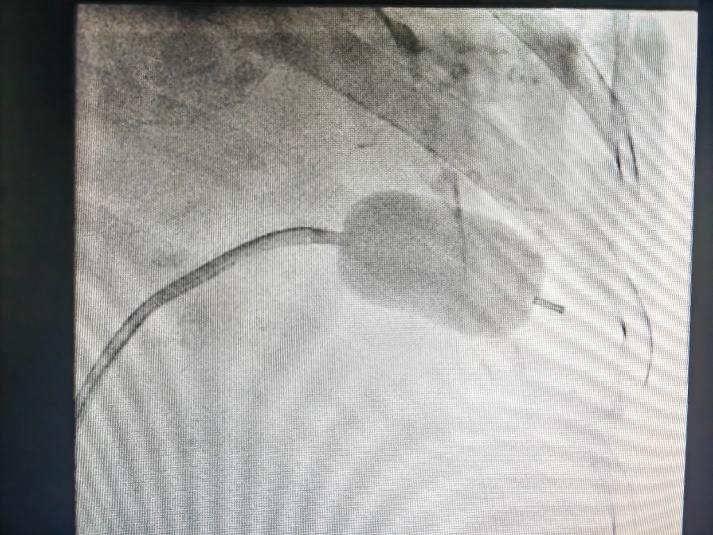

图四:球囊对狭窄的二尖瓣进行扩张

此例手术由姚晓伟主任医师、韩稳琦主治医师、赵永勇主治医师通过心腔内超声指导下进行,通过心腔内超声精准构建心脏模型、直视下穿刺房间隔,后通过心腔内超声及左心房造影寻找狭窄的二尖瓣瓣口,并指引二尖瓣球囊扩张导管顺利经狭窄的二尖瓣口至左心室,在心腔内超声的指引下选择最佳位置以26mm球囊导管反复扩张狭窄的二尖瓣。术后第二天复查心脏超声,患者二尖瓣瓣口面积由术前0.67cm2扩大到术后1.69cm2,二尖瓣跨瓣压差由术前22mmHg降低至术后的16mmHg,左房前后径由术前94mm减小至术后92mm,左房左右径由术前109mm减小至术后102mm,并且球囊扩张后未引起明显的二尖瓣反流,患者心功能明显改善,自觉症状明显好转出院。

经皮二尖瓣球囊扩张成形术因其不需要开胸、创伤小、术后恢复快、严重并发症少见、作用明显而被广泛应用于临床治疗二尖瓣狭窄。心血管内二科独立成功完成此例罕见、复杂、高风险二尖瓣狭窄患者心腔内超声指引下的经皮二尖瓣球囊扩张成形术,标志着三级片